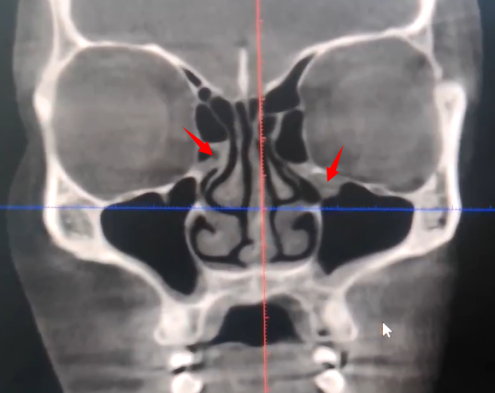

图片

图注:A:显示右侧筛窦内软组织阴影堵塞以及右侧上颌窦顶壁粘膜增厚;B:上颌窦内阴影,有液-平面,提示上颌窦积液。

• 鼻窦CT并不能很好区分急性和慢性鼻窦炎。

因为不管是急性还是慢性鼻窦炎,我们均能够从内镜上观察到鼻窦内阴影,所以一定要密切结合孩子的病史来判断。

• 影像学诊断“鼻窦炎”≠临床诊断鼻窦炎。

常有因为其他原因完善CT检查,发现鼻窦内粘膜增厚的情况,但孩子可能并无任何鼻窦炎的症状,我们并不诊断鼻窦炎。

如上图所示,齿科拍摄牙片时发现筛窦粘膜有轻微增厚(箭头所示),但孩子仅在2周前有过“感冒”表现,目前已经自愈。这种情况考虑是急性鼻窦炎恢复期,不一定需要治疗。